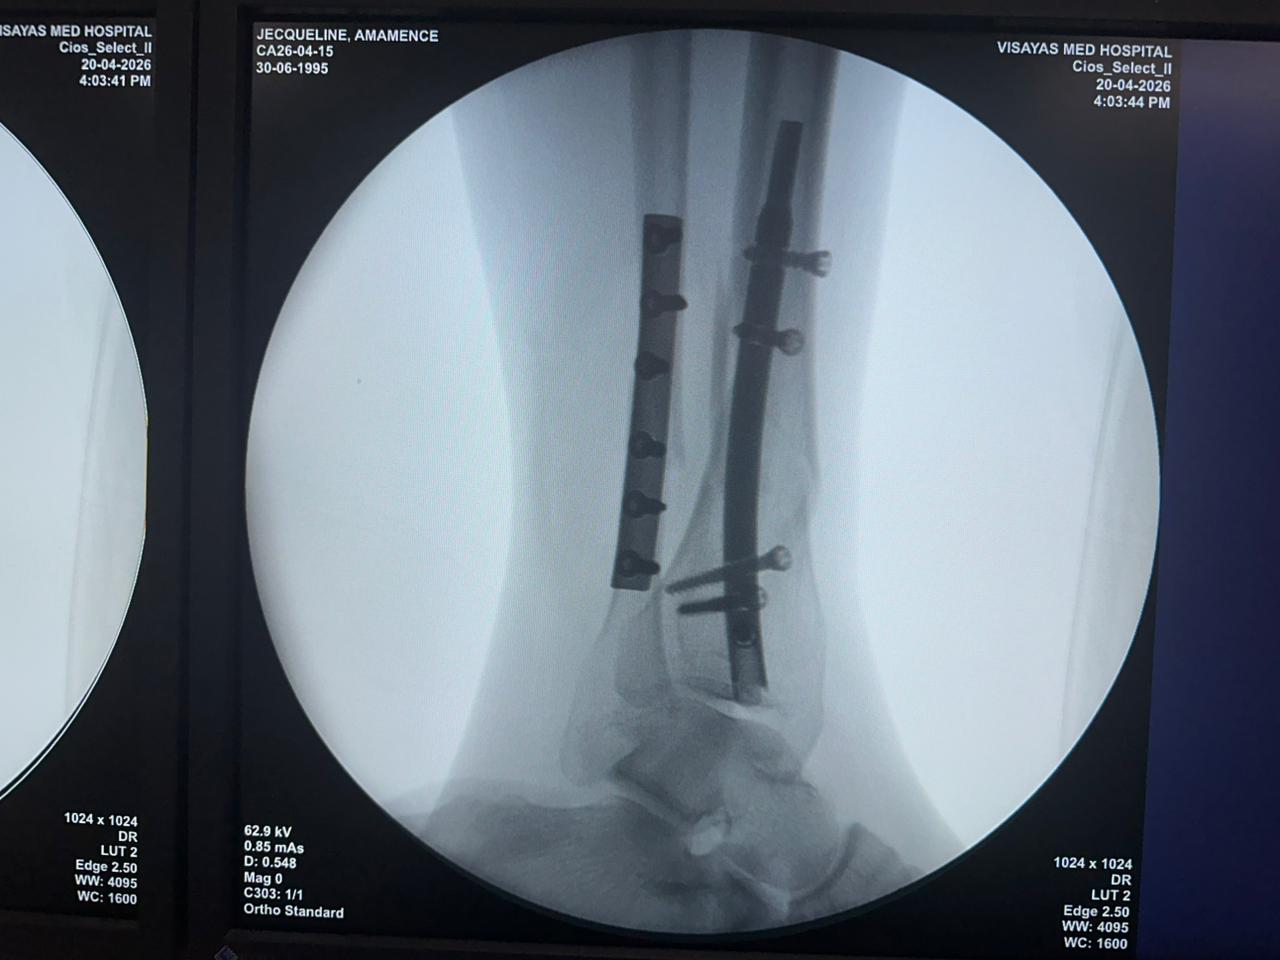

Estudio de caso de fijación de clavo tibial distal con soporte de placa para peroné

Imágenes:

Radioscopia intraoperatoria con arco en C, vistas AP y lateral

Este caso involucró la fijación de la tibia distal utilizando un clavo tibial distal intramedular. La fluoroscopia intraoperatoria confirmó la posición del clavo, los tornillos de bloqueo distales y la fijación de la placa del peroné.

clavo-tibial-distal-fluoroscopia-intraoperatoria-czmeditech (2)

clavo-tibial-distal-fluoroscopia-intraoperatoria-czmeditech (3)